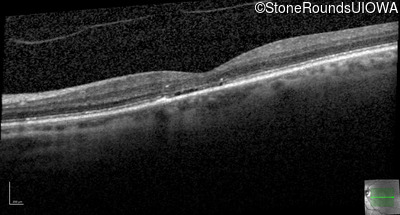

The clinical features supporting the diagnosis of blue cone monochromacy in this patient include: stable reduced acuity, photophobia and very poor color vision since early childhood, a normal fundus appearance, normally sighted parents and three similarly affected male relatives on the maternal side of his family.

Age at visit: 55 years

Age at visit: 56 years